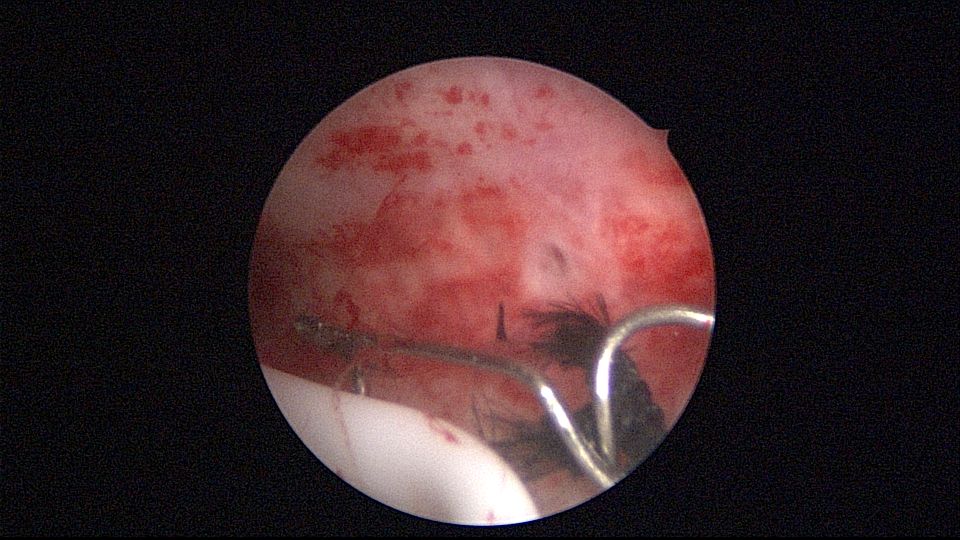

患者40岁,G0P0,原发不孕10+年,20+岁严重痛经,多家医院行腹腔镜手术治疗腺肌症合并多发性肌瘤,宫腔镜切除内膜息肉,前后肌注GnRH-a6针,痛经明显缓解。2017年试管助孕一次,失败,放弃生育需求,现要求放置曼月乐环并固定。2024年5月行宫腔镜下曼月乐不锈钢挂钩固定,子宫前位,宫深7cm,宫腔形态正常,宫内膜正常,双侧输卵管开口可见,将曼月乐环用4号丝线与挂钩连接并固定于宫底(第一次做宫腔镜下节育环固定,没有想到利用曼月乐尾丝连接环)。2024年6月复查B超,曼月乐固定装置扎入宫底肌层0.46cm,环位置正常,2025年5月复查B超,曼月乐顶端距宫底1.5cm。